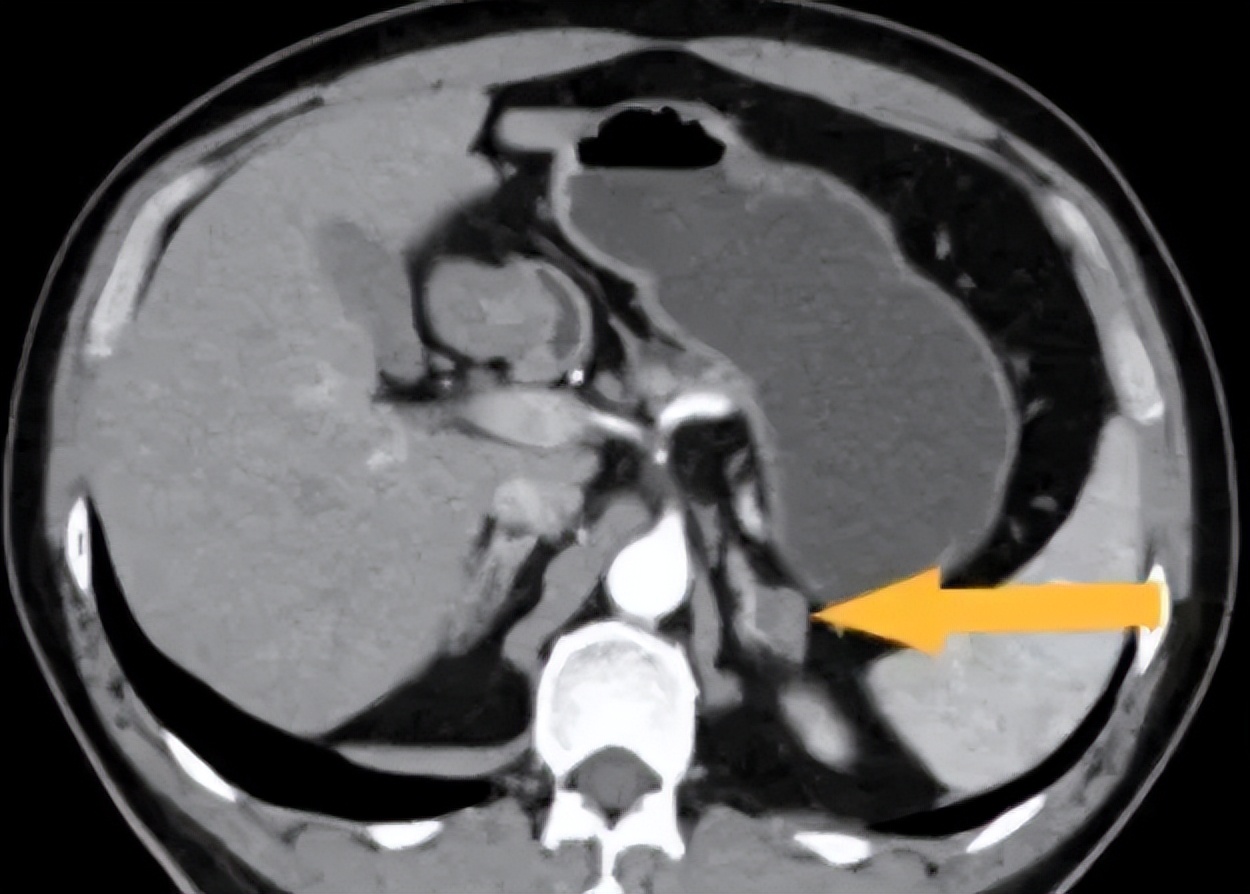

据入院检验检查结果,该患者明确为肾上腺腺瘤导致的原发性醛固酮增多症,引起继发性高血压。为什么肾上腺腺瘤会引发高血压,让我们先了解高血压,

肾上腺调控血压的机制

肾上腺在体内属于内分泌器官,会分泌激素引起心脏兴奋,心脏血液输出量增加,导致血压升高。因此当肾上腺出现病变时,如出现肾上腺腺瘤、肾上腺皮质增生,肾上腺激素分泌紊乱,则会导致血压升高、控制不佳的情况发生,严重者会导致心脑血管意外!